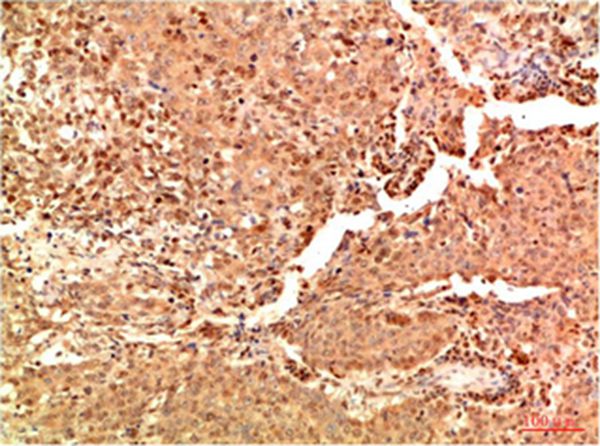

分类: 科研抗体货号: P43821别名:应用: WB,IHC反应种属: Human,Mouse,Rat